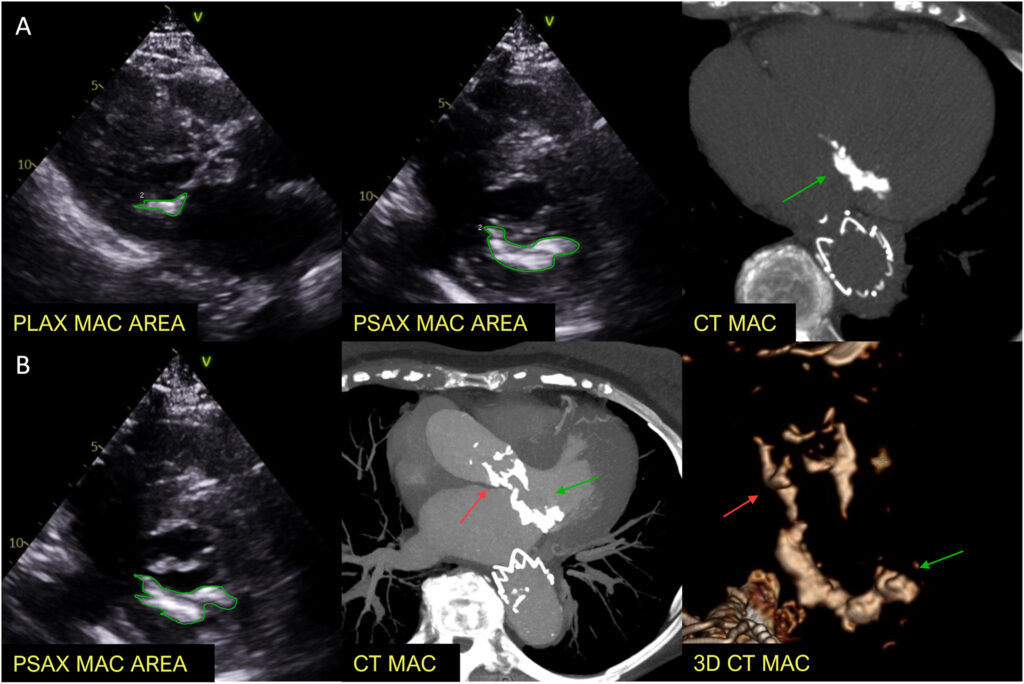

Para tanto, os participantes tiveram a área da calcificação do anel mitral medida tanto no eixo curto quanto no eixo longo da janela paraesternal em frame único com a melhor visualização do anel mitral.

Se a calcificação estivesse presente em segmentos descontínuos, esses eram medidos separadamente. Além da quantificação da área, foi também realizado a porcentagem do total da calcificação em relação a circunferência do anel valvar.

Já na TC, a quantificação da calcificação foi realizada através do escore de Agatston.

Nesta análise, as calcificações da valva aórtica e submitral foram subtraídas na análise tridimensional da TC.

Um desafio observado durante a avaliação foi a identificação da extensão real de toda a calcificação pela ecocardiografia. Isso ocorreu em razão de que as imagens eram focadas no plano dos folhetos valvares em único frame, contudo isso poderia não necessariamente captar todo o acometimento da MAC. Sendo assim, recomenda-se que a avaliação englobe não só o frame no plano dos folhetos da valva mitral, mas sim de todo o aparato mitral.